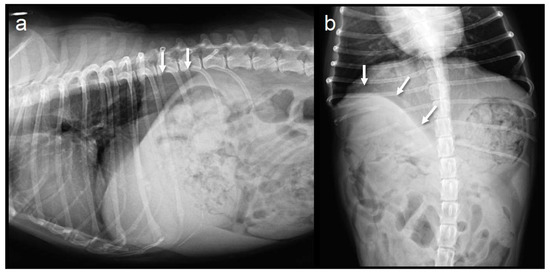

Figure 3.

Abdominal radiographs at the 6-month follow-up. The suture line of the diaphragm and thoracic wall is visualized (arrows). (a) Lateral view; (b) Ventrodorsal view.